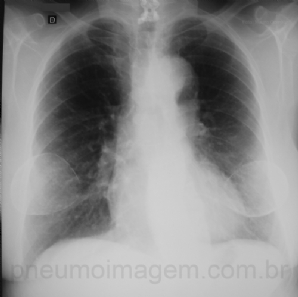

CASO CLÍNICO #18

Em avaliação de rotina foi encontrada esta alteração radiológica. Qual o seu diagnóstico? Deixe seus comentários abaixo. ***** This radiological alteration was found in a routine evaluation. What is your diagnosis? Write your comment below.